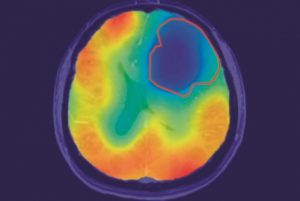

Mehr erfahren zu: "Hirntumore mit Sauerstoff sichtbar machen" Hirntumore mit Sauerstoff sichtbar machen Wissenschaftler vom Deutschen Krebsforschungszentrum haben eine neue Technik entwickelt, um mithilfe von Sauerstoff Gehirntumoren im Magnetresonanztomografen (MRT) besser erkennen zu können. Dabei setzen sie auf eine Besonderheit im Stoffwechsel der […]